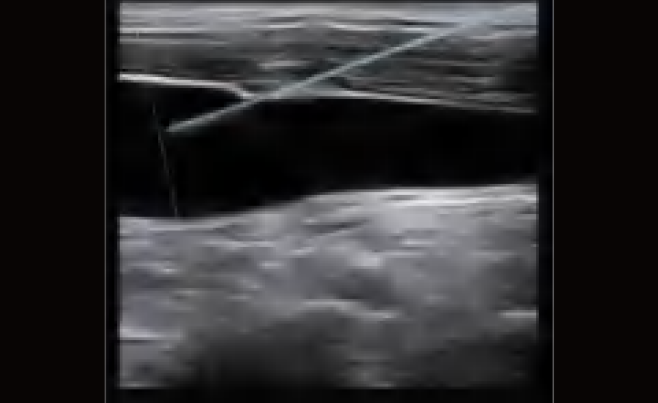

El DW-L50 Exp, impulsado por la avanzada plataforma de ultrasonido ST-U, ofrece imágenes ultra claras en todo momento. Con una movilidad y adaptabilidad sobresalientes, funciona de manera fiable en diversos entornos clínicos complejos. Su introducción permite que más instituciones médicas accedan a tecnología de ultrasonido rentable y de alto rendimiento.